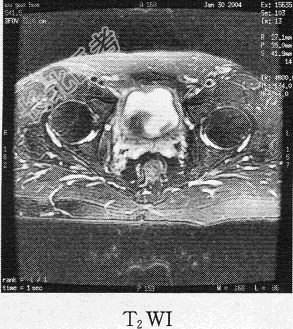

- 单项选择题患者男,76岁。反复无痛性肉眼血尿3个月, MR图像如下,最有可能诊断为

C、膀胱癌